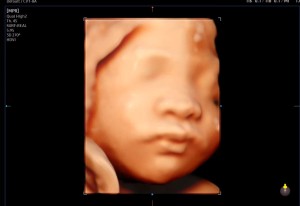

입초 두번째 만에 얼굴보여준 너!

닉네임_윤*영_5

2025-08-22

30주 입체초음파입니다 :)

이레IYRAE

2025-08-21